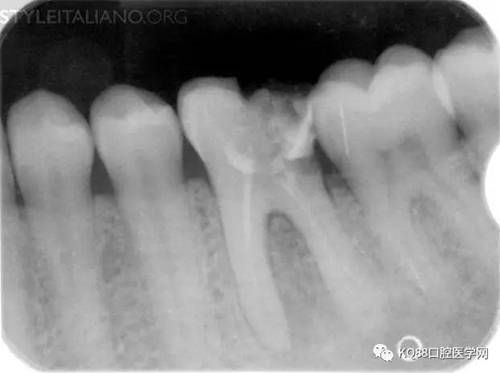

Img. 1 - The occurrence of pain and/or swelling after endodontic treatment is different in two circumstances: whether the pulp was vital before treatment or not. In the case of vital pulp, pain could be associated with the persistence of pulpal remnants in the root canals. This can happen as a consequence of missed canals, or of a less than optimal shaping and cleaning technique. Missed canals are often associated with a lack of accuracy in designing the access cavity. Besides the case of an erroneously short working length, the widespread use of standardised instrumentation can lead to underestimate the presence of oval shaped, or unusually wide canals. An inaccurate apical gauging and finishing of these canals can leave uncleaned canal space, and inflamed pulp remnants can cause pain.

Case 1: In this patient, persistent pain was present after endodontic treatment of a vital tooth. The periapical x-ray showed an inadequate shaping of the distal root canal, regarding both the working length and the apical taper.